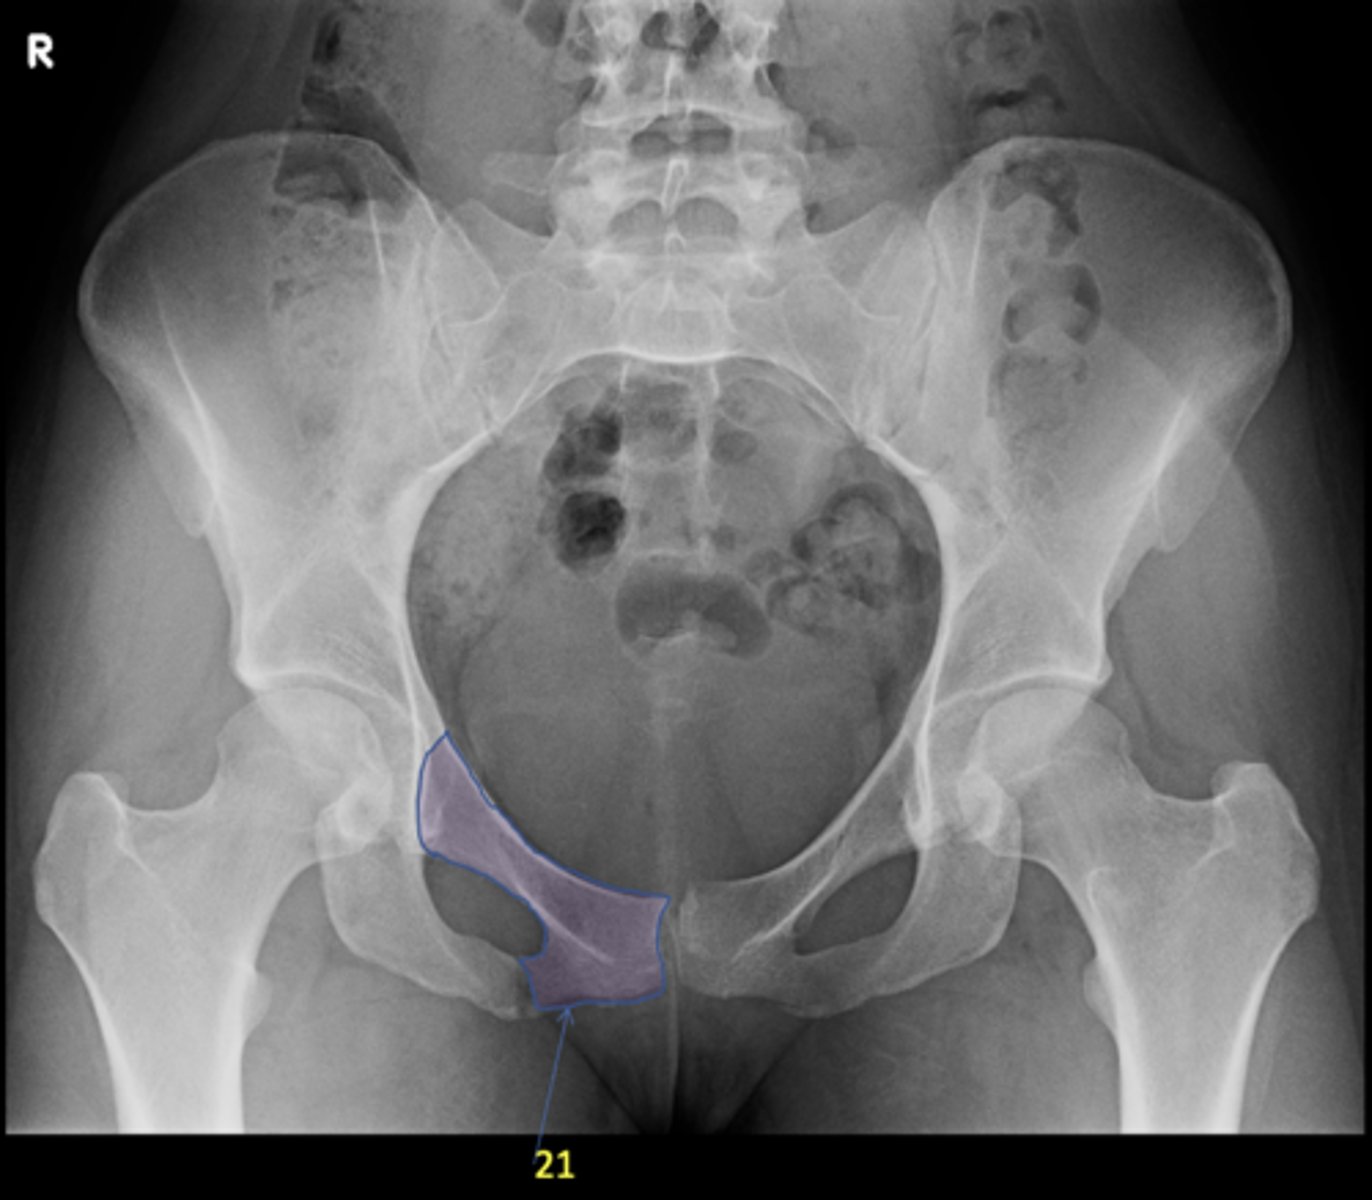

21

Left superior pubic ramus

ID 24

<p>ID 24</p>